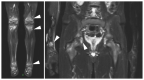

Autoinflammatory disorders are commonly characterized by seemingly unprovoked systemic inflammation mainly driven by cells and cytokines of the innate immune system. In many disorders on this spectrum, joint and bone involvement may be observed and imaging of these manifestations can provide essential diagnostic information. This review aimed to provide a comprehensive overview of the imaging characteristics for major diseases and disease groups on the autoinflammatory spectrum, including familial Mediterranean fever (FMF), Behçet disease (BD), crystal deposition diseases (including gout), adult-onset Still's disease (AoSD), and syndromatic synovitis, acne, pustulosis, hyperostosis, and osteitis (SAPHO)/chronic recurrent multifocal osteomyelitis (CRMO). Herein, we discuss common and distinguishing imaging characteristics, phenotypical overlaps with related diseases, and promising fields of future research.